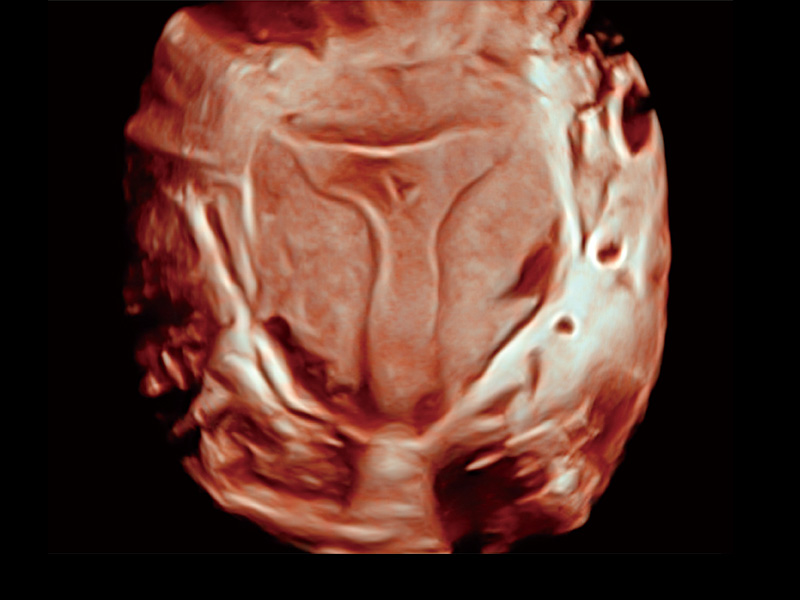

临床图

单角子宫

子宫内膜息肉